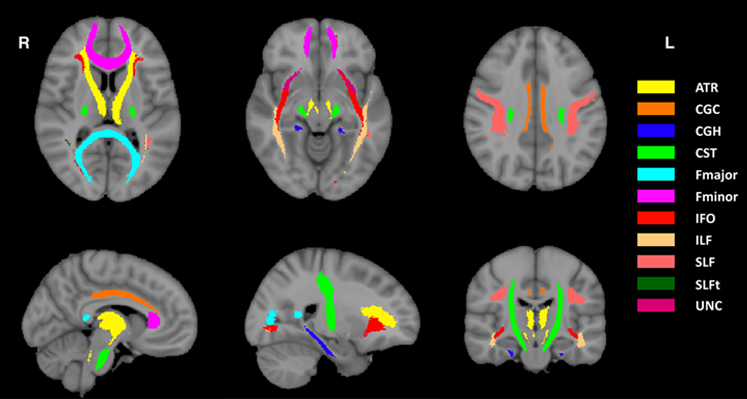

Our software is flexible and easy to use. In addition to the whole brain, region of interest (ROI) analysis can also be conducted to evaluate the regional DDF for local anatomical information. As an example, DDFs can be separately computed for all the ROIs of the JHU white matter tractography atlas (probability threshold at 0.25) (see the figure).

Figure: JHU white matter tractography atlas (probability threshold at 0.25)

ATR, Anterior thalamic radiation; CGC, Cingulum (cingulate gyrus); CGH, Cingulum (hippocampus); CST, Corticospinal tract; Fmajor, Forceps major; Fminor, Forceps minor; IFO, Inferior fronto-occipital fasciculus; ILF, Inferior longitudinal fasciculus; SLF, Superior longitudinal fasciculus; SLFt, Superior longitudinal fasciculus (temporal part); UNC, Uncinate fasciculus